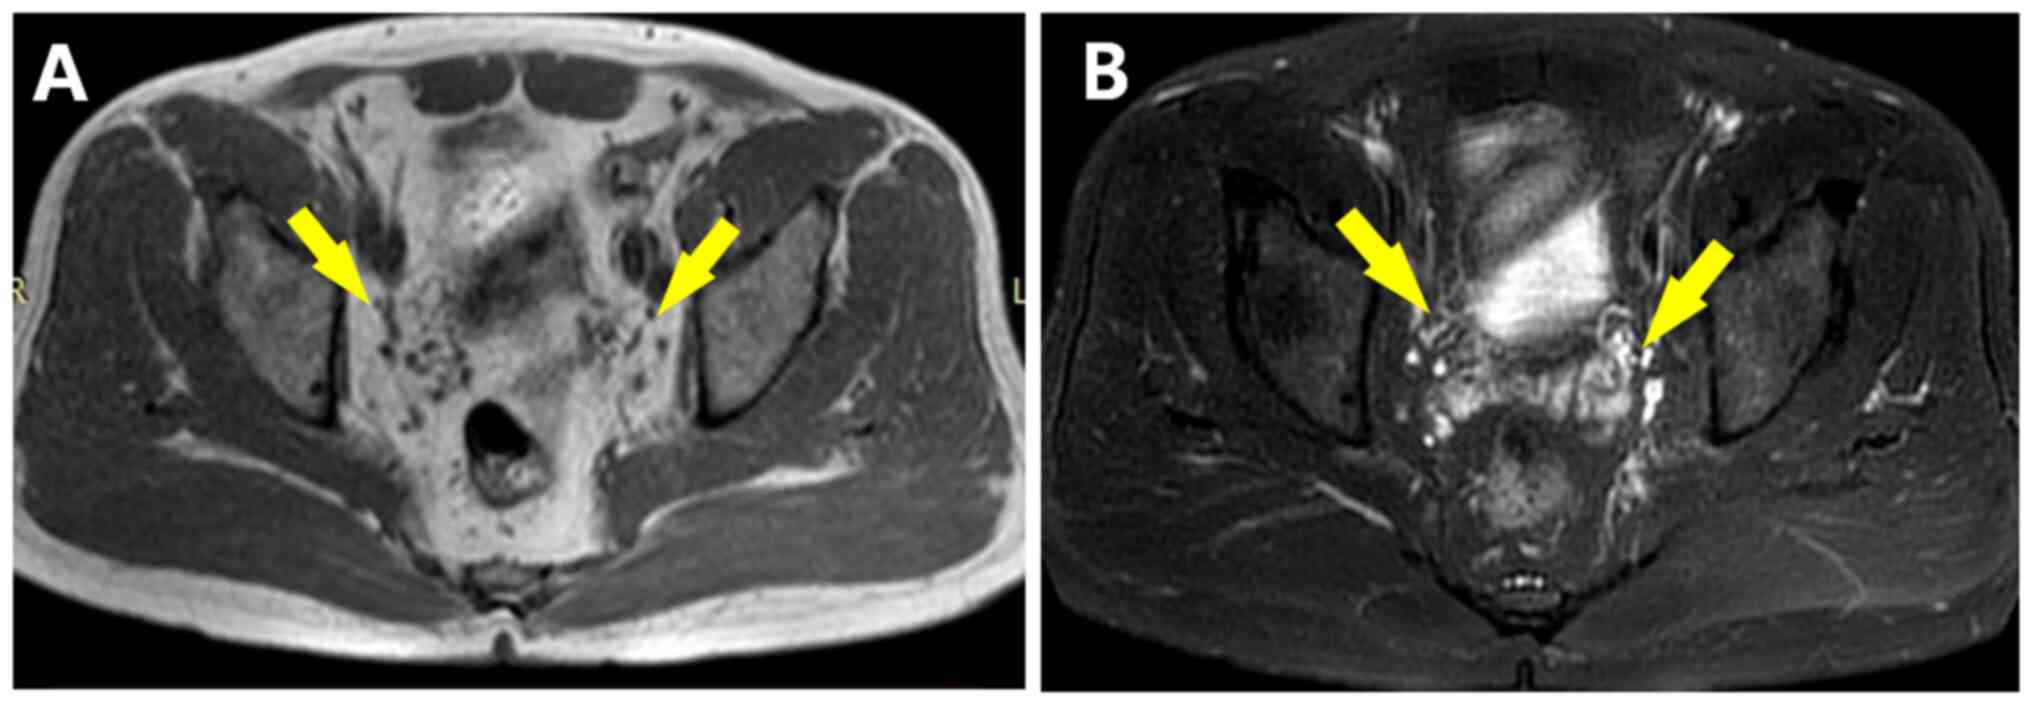

In September 2021, a 55-year-old male patient sought medical attention at Xiangyang No. 1 People's Hospital (Xiangyang, China) due to complaints of ‘lower back pain for one week’, without any symptoms such as painful urination, gross hematuria, frequent urination and urgency of urination. The medical record indicated a history of oral medication therapy for hypertension and hypothyroidism. Physical examination on admission found no obvious abnormality. MRI showed symmetrical soft tissue masses around the bilateral distal ureters, with equal signal on T1-weighted imaging (T1WI) (Fig. 1A), slightly higher signal on T2WI (Fig. 1B) and significant enhancement (Fig. 1C and D). In the diffusion-weighted imaging sequence (DWI), the lesions had a high signal (Fig. 1E), while they had a low signal in the apparent diffusion coefficient (ADC) image (Fig. 1F). The size of the larger mass was 25x23x35 mm and the smaller one was 18x21x23 mm(right). Magnetic resonance urography indicated stenoses of bilateral distal ureters and proximal hydronephrosis (Fig. 2). The serological results revealed that the IgG4 level was 8.690 g/l (0.03-2.01, for IgG4-RD cutoff, >1.35 g/l), IL-6 level was 7.1 pg/ml (normal range: 0.1-2.9 pg/ml)and IgE level was 255.10 IU/ml (normal, ≤100 IU/ml). Due to consideration of IgG4-RD, prednisone acetate tablets (40 mg/day) and mycophenolate mofetil dispersible tablets (1 g/day) were administered. After 30 days, the IgG4 level had dropped to 4.610 g/l and the IgE level had decreased to 130.60 IU/ml. After 6 months, the masses had disappeared completely in the follow-up MRI (Fig. 3A and B). In May 2022, laboratory examination at another hospital indicated that IgE and IL-6 had dropped to normal. The patient continued to take mesalazine dispersible tablets (0.5 g/day) to prevent relapse. According to an MRI scan conducted in April 2023, there was no significant recurrence of the lesions observed at the distal ends of both ureters.

Follow-up. (A) T1W1 and (B) T2WI magnetic resonance imaging after 6 months of treatment, indicating that the masses had completely disappeared. T1WI, T1-weighted imaging. Yellow arrows indicate the previous location of the soft tissue masses.